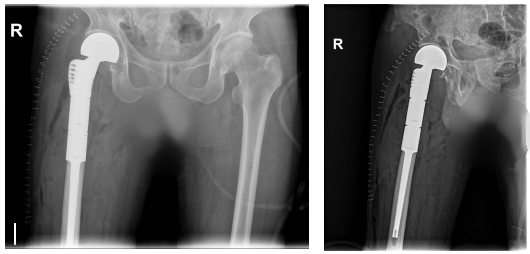

术前影像显示:肿瘤已经侵及患者右大腿上段并病理性骨折

术后影像显示:肿瘤完整切除,股骨上段成功植入肿瘤假体